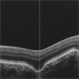

- choroidal defect, excavation

- Optical coherence tomography system

- Right eye raster OCT image of a 46-year-old high myope (-8Dsph) showing conforming variety of foveal choroidal excacation.